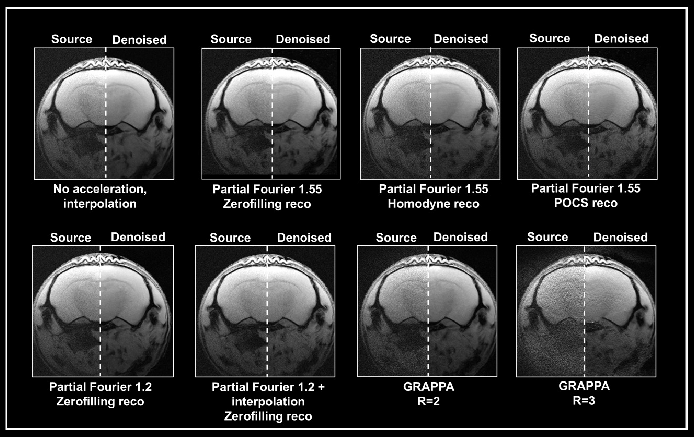

Multiple methods to accelerate MRI acquisitions by employing temporal or spatiotemporal redundancy of the images have been used in the literature.6 Approaches such as parallel imaging deliver structured noise in the reconstructed image as the decreased data sampling and noise amplification result from the parallel reconstruction algorithm.1

Ex vivo brain data were obtained with either partial Fourier or the multi-coil generalized auto-calibrating partial parallel acquisition (GRAPPA) approach (Fig. 5). Data obtained without acceleration served as a reference. Acceleration translated into an up to 3-fold decrease in acquisition times compared to the protocol when no averaging was used.

Figure 5. Denoising of accelerated brain data. Ex vivo T1-weighted FLASH data of a fixed mouse head were acquired at 9.4 Tesla. Data were either acquired with no acceleration, with partial Fourier (in Read), partial Fourier and interpolation (1.35 in Read and Phase), or with multi-coil parallel imaging technique GRAPPA. For GRAPPA, an acceleration factor (R) of 2 and 3 was chosen, respectively. Partial Fourier images were reconstructed either with zerofilling, homodyne, or POCS, as indicated. All images are shown with no denoising (Source) and after denoising (Denoised) with a Strong network, applying a pre-denoising level of 50% and denoising level of 70%. Image Credit: Bruker BioSpin Group

A denoising level of 70% led to more residual noise in data obtained with a partial Fourier 1.55 compared to data obtained without acceleration. The effect was most significant in homodyne-reconstructed data and lower in zero-filled data. Furthermore, denoising of these accelerated datasets led to image blurring, which was also most robust in homodyne-reconstructed images and lowest in images that were reconstructed with zero-filling.

Obtaining images with partial Fourier 1.2 led to less residual noise and normal image appearance when denoised with 70%. Denoising was ineffective, however, when combining a partial Fourier with interpolation (1.35 in Read and Phase) with the source and the denoised image having similar appearance.

Grappa acceleration led to noisier images than in acquisition with partial Fourier. Reconstructing the obtained data with the denoising algorithm removed noise from the GRAPPA image obtained with an acceleration factor 2.

However, the noise is not fully removed in the image obtained with an acceleration factor 3. Furthermore, reconstruction artifacts and loss of tissue contrast unrelated to the denoising reconstruction are visible.

This demonstrates that the algorithm may be unable to work with data that has a noise characteristic different from the noise that the networks have been trained with (i.e., without acceleration and interpolation). Yet, the outcome is dependent on the selected acquisition and reconstruction parameters.